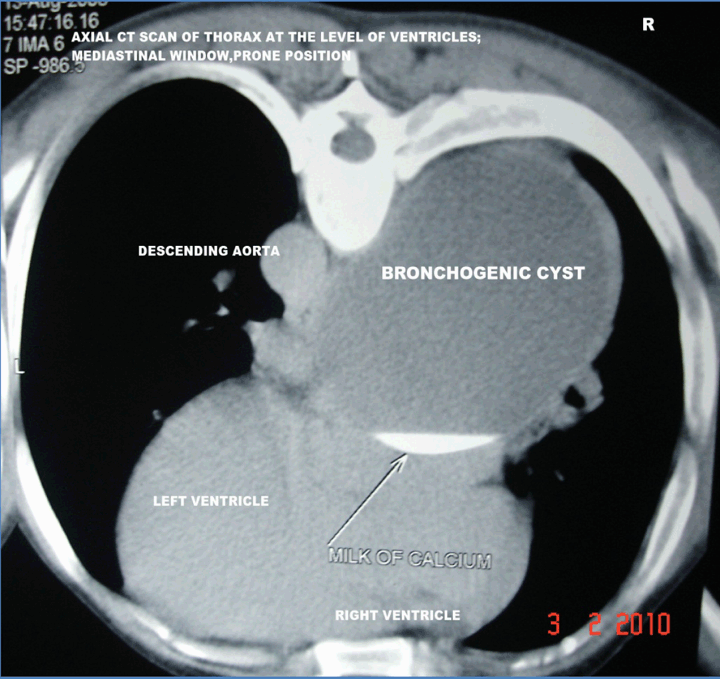

A 35-year-old male patient was presented with sense of heaviness in chest and shortness of breath even at rest for past two years. He gave history of intermittent low grade fever, cough, right sided pain chest since his adolescence and was frequently treated with antibiotics. Chest X-ray showed a right sided mediastinal mass with ipsilateral peripheral pleural calcification in the mid/lower zone. Electrogram and echocardiography were within normal limits. The CT scan of thorax showed a right sided posterior mediastinal, unilocular, cystic mass lesion having diameter of 10.9x8 cm with a homogeneous, increased fluid attenuation value of +15 HU. (Figure 1) On contrast study the cyst was thin-walled, nonenhancing except a small part of its right edge suggesting focal thickening of inflamed mediastinal pleura or compressed part of lung adjacent to the cyst. (Figure 2) A fluid was found at its dependent part, both in supine and in prone position due to presence of a small amount of higher density fluid. (Figure 1) (Figure 2) and (Figure 3) A focus of calcification was found in a part its periphery. (Figure 3) Absence of air within the cyst proved that the cyst was noncommunicating. Right intermediate bronchus was partially compressed and slightly displaced by the mass. (Figure 4) Associated ipsilateral periopheral pleural calcification was present. The CT guided aspiration revealed its content to be whitish, opalescent fluid with high protein, epithelial cells, amorphous calcium. Culture report was negative. Fibreoptic bronchoscopy revealed mucosal thickening and mild narrowing of lumen of right intermediate bronchus due to extrinsic compression. Bronchoscopic biopsy specimen revealed inflammatory changes and no malignant cell was detected.

Figure 2: Axial computed tomography scan of thorax at the level of ventricles; mediastinal window, prone position.